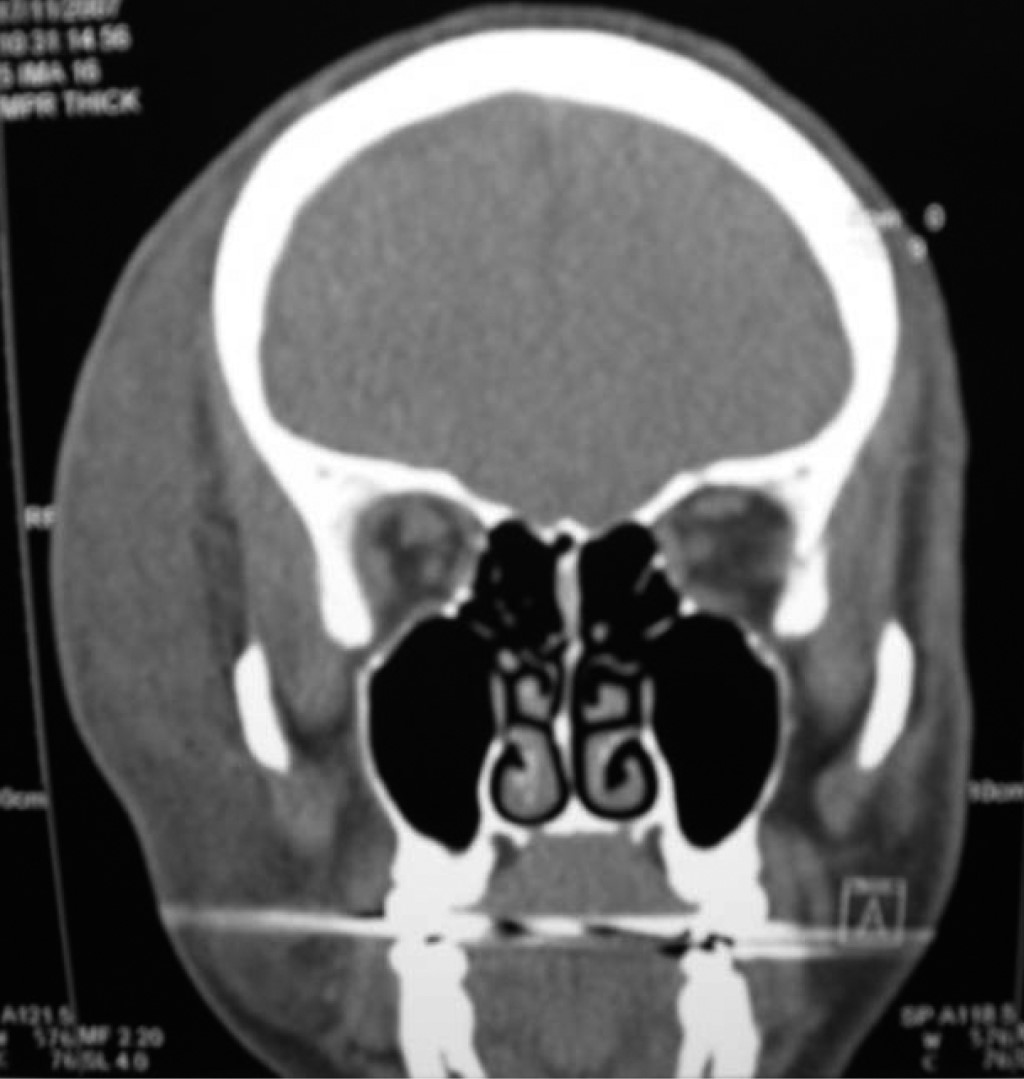

Periorbital cellulitis

Periorbital cellulitis is a relatively common and potentially serious ophthalmologic emergency, defined as an infection anterior to the orbital septum involving the eyelid and periocular soft tissues. We present two cases of periorbital cellulitis, with a review of the literature, management guidelines and sequelae of this condition. A 46-year-old man who had periorbital pain, pruritus, progressive increase in volume in the right orbital region, with a history of self-medication. The patient used a toupee. Intense epiphora, chemosis, hyperthermia, and leukocytosis were found, when he was admitted to hospital. Cellulitis, secondary to skin trauma, was diagnosed. This produced an ulcer and a severe inflammatory process in the right side of the face, with significant involvement of the right orbital region. It was managed jointly with the infectology service. He presented eschar on the right upper eyelid, which required surgical lavage, debridement, and application of a full thickness graft. Given the complexity of the orbital region, this case raised the importance of establishing timely management aimed at solving the etiology of the problem and joint management with different specialties, to avoid severe sequelae, such as vision loss or sepsis. In the same way, a 77-year-old woman with a history of facial trauma, who presented an inflammatory process of 4 months of evolution, was treated. A foreign body (wood) was found in the upper left eyelid, which raised the importance of managing these injuries by a specialist for optimal management.

Figure 1

Figure 2

Figure 3

Figure 4

Figure 5

Figure 6

Figure 7

Figure 8

Figure 9

Figure 10

Figure 11

Figure 12

Figure 13